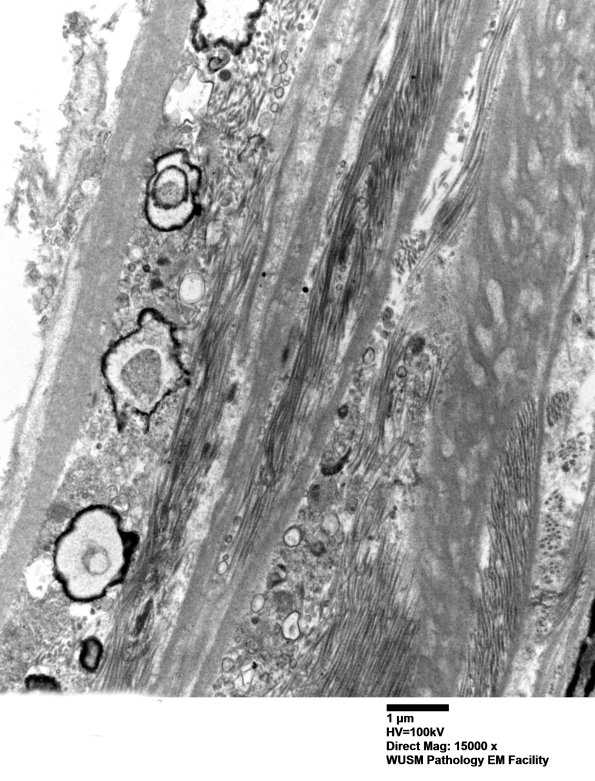

The perineurium shows numerous focal calcifications of unknown pathogenesis. (electron micrographs)